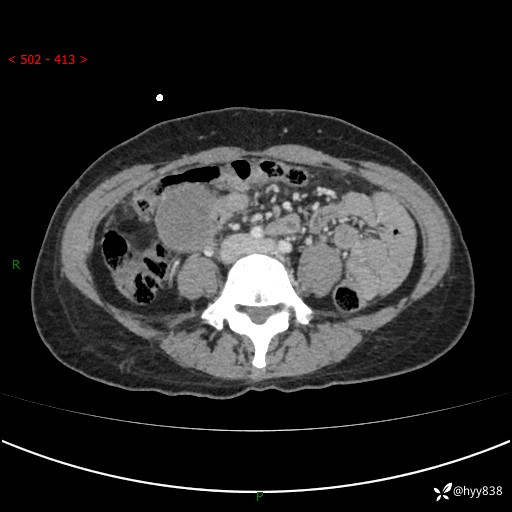

年轻女性,发现腹腔肿物1周。圆圆的肿物,诊断有难度---结果公布~

现病史:患者自诉于1周前无明显诱因出现剑突下间断性隐痛,尚可忍受,不向其它部位放射,无恶心呕吐、腹泻便秘等不适,于当地市第二人民医院就诊,行CT结果示:1.右中腹占位,间叶组织来源可能2.小肠梗阻3.盆腔积液4.腹腔积液5.副脾6.肝囊肿;于荆州二医行抗炎,抑酸,护胃,补液等对症支持治疗;患者病情好转,今为求进一步诊治,遂来我院门诊就诊,门诊以“腹腔肿瘤”收入院。 起病以来,患者精神、睡眠、饮食一般,大小便正常,近期体力体重无明显改变。

腹部CT增强(外院平扫)